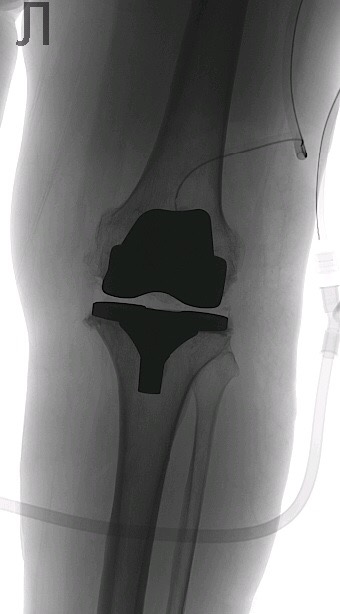

Рекурвация коленного сустава: рентгеновские снимки и объяснения